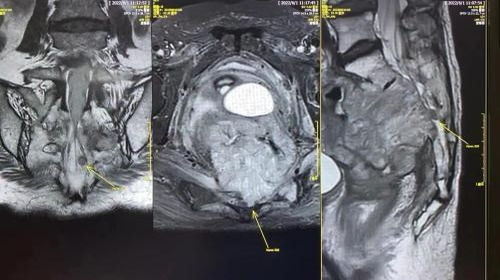

经过仔细检查评估,邱剑光发现马姨的肿瘤十分巨大,达20厘米×15,主要在盆腔,累及膀胱、子宫阴道、代直肠、骶骨1-4,庆幸的是没有明确的远处转移征象。邱剑光召集团队组织了科内病例讨论会,认为这个病例属于盆腔局部晚期复发肿瘤,理论上有进行全盆腔脏器切除+全骶骨切除来达到肿瘤完整切除的可能。

盆腔巨大肿瘤,累及膀胱、输尿管、子宫阴道、代直肠、骶骨1-4